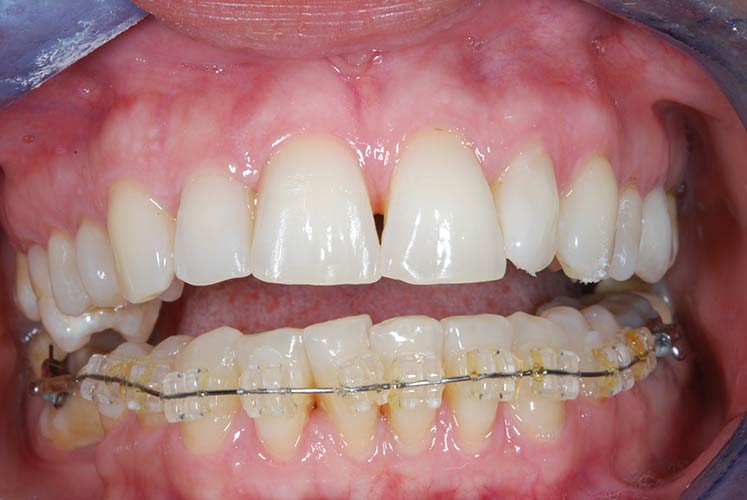

Trattamento ortodontico nell'adulto con intrusione del I° molare superiore mediante l'utilizzo di mini impianti

Riabilitazione gnatologica, ortodontica ed estetica

Durata del trattamento: un anno

Trattamento ortodontico nell'adulto